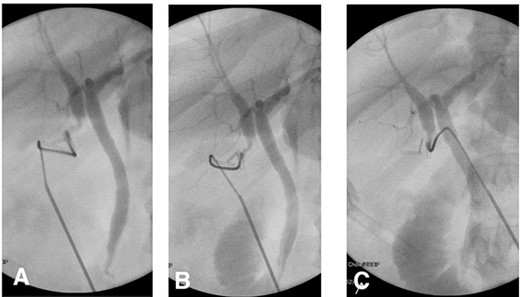

Intraoperatively, standard 4 port laparoscopy was performed, and an oedematous gallbladder was encountered which required a combination of sharp and blunt dissection. The hepatocystic triangle dissection was challenging due to severe fibrosis. A ductal structure was isolated and seen to be entering the gallbladder which was subsequently clipped and a ductotomy performed. After cannulation of the ductotomy, an intraoperative cholangiogram (IOC) revealed what appeared to be a duplicated CHD separating the right and left hepatic drainage systems with a communicating aberrant extrahepatic duct (Fig. 2). Of note, no filling defects were appreciated in the distal common system.

(A) IOC showing the point of cystic duct cannulation with retrograde contrast injection revealing a connection with a duplicated CHD draining the right system and another CHD draining the left system proximally. (B) and (C) Further contrast injection demonstrating no filling defects in the distal common system with good flow into the duodenum.